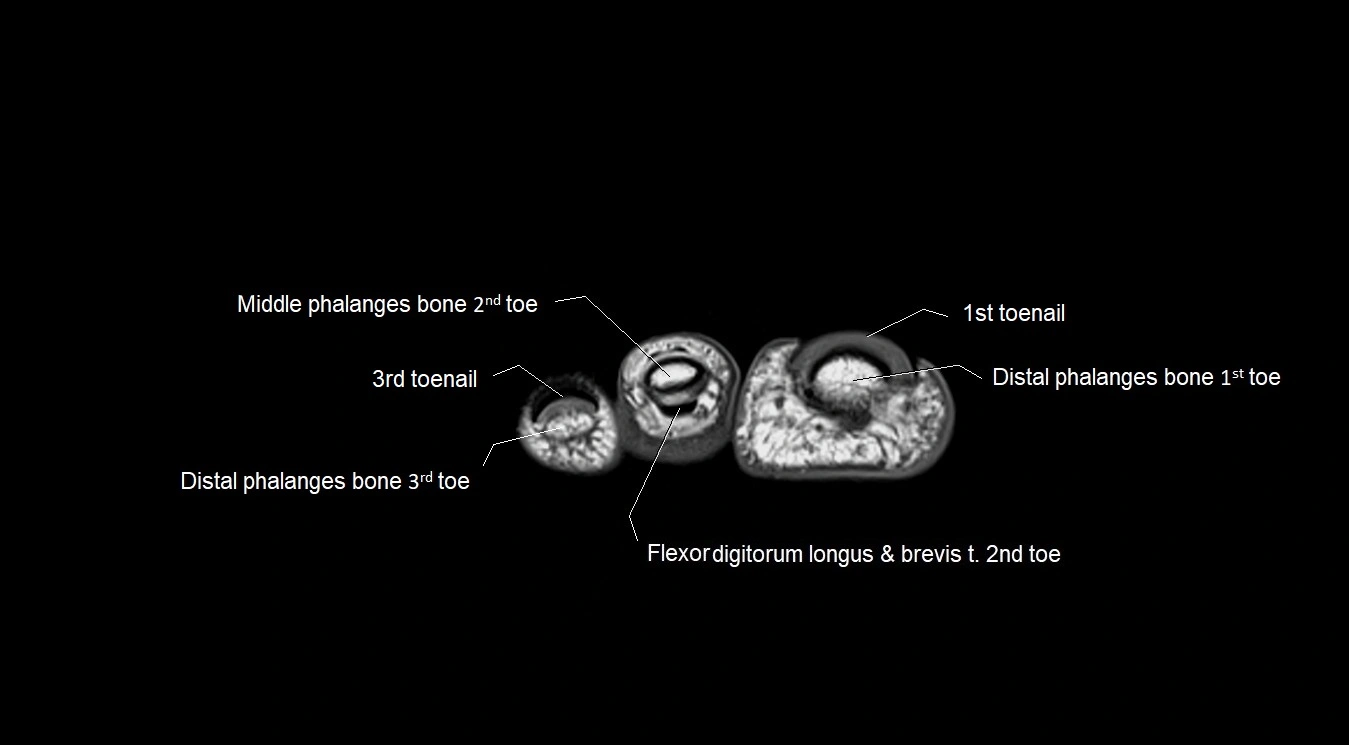

MRI image